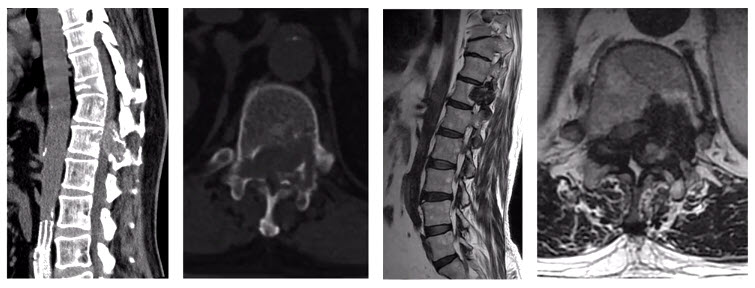

Let’s consider another case. It was a 55-year-old male presenting with incomplete paralyzed, Frankel C. Osteoblastoma of T12 was diagnosed by biopsy. It was Enneking stage 3 lesion. We did an intentional intralesional en bloc spondylectomy, then radiotherapy after the surgery. There was no recurrence in the two-year follow-up.

But sometimes things are more complicated. Another case involved a 33-year-old female. The chest X-ray examination found an osteogenic spinal lesion. The CT scan showed osteolytic lesions of T9 left vertebral body, facet joints and rib, with extensive reactive bone formation.

There was obvious spinal cord compression, and the PET/CT revealed extensive uptake.

We did a CT-guided biopsy. Although we consulted the result in three hospitals, the pathologists failed to give us a definite diagnosis, whether it was osteoblastoma or a low-grade osteosarcoma.

So, we treated it as if it was malignant. We did an anterior-posterior approach sagittal en bloc resection of the T8 to T10. In the anterior approach, we dissected the tumor. In posterior approach, we transected the body with an ultrasonic cutter. We resected three segments en bloc. The margin was sufficient, not only pathologically, but also by CT scan.

The postoperative pathological diagnosis is still unclear. The pathologists gave us four diagnoses: osteoblastoma, epithelioid osteoblastoma, low-grade osteosarcoma, or even osteomyelitis.

Nevertheless, the patient was doing well in the 2-year follow-up. There is no recurrence.